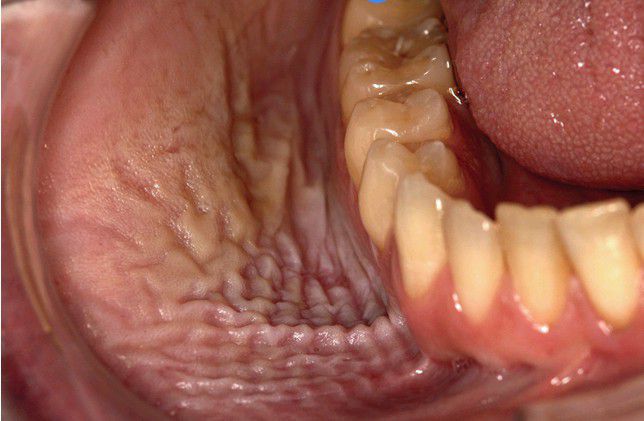

Tobacco Pouch Keratosis, Severe

. A somewhat leathery, white, fissured plaque of the right mandibular vestibule, which was located in the area of chronic chewing tobacco placement.